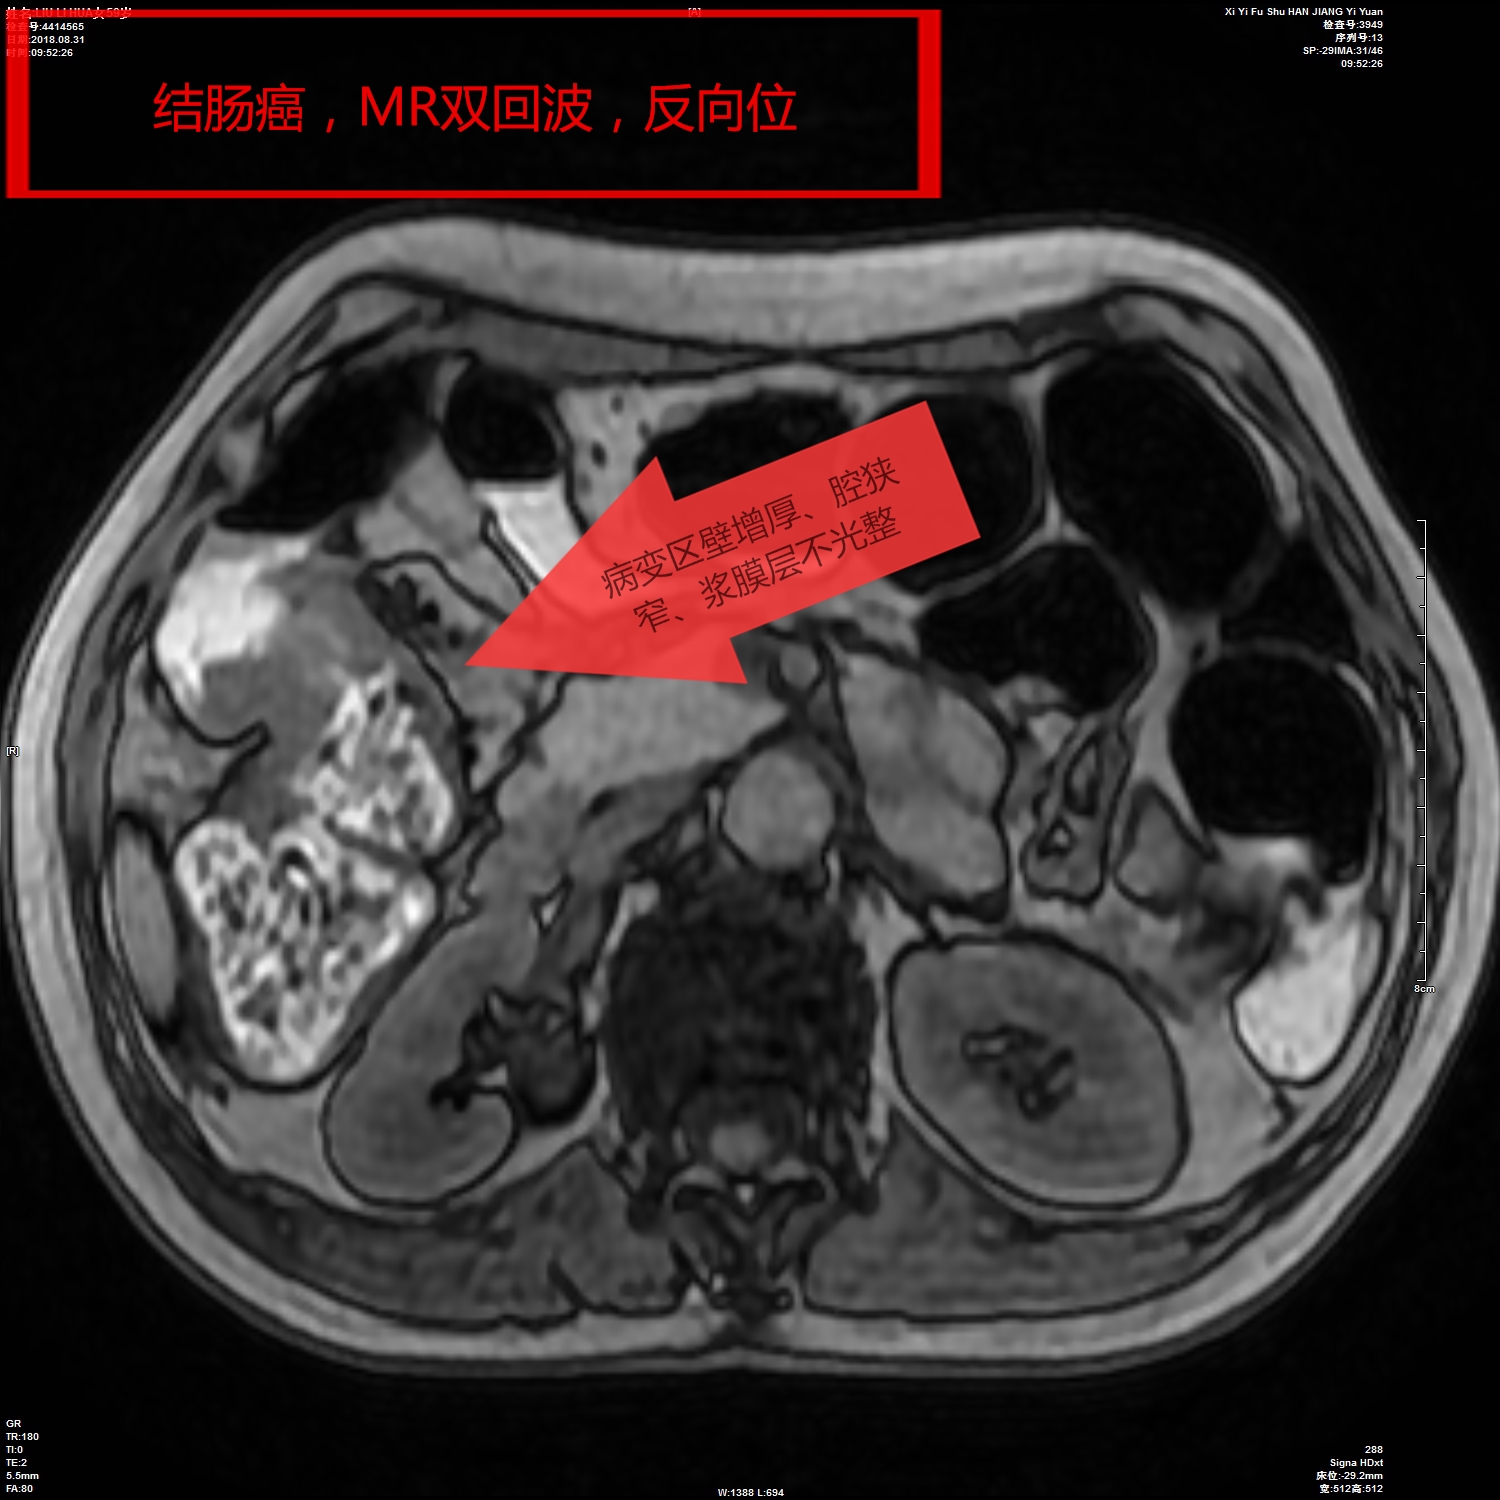

我院影像科从2018年开始,利用CT、MR分辨率高、成像方法多的特点,开展胃肠快速充盈低张CT、MR检查技术,通过多序列、多窗位、多方位检查,对肠壁、及其腔内腔外病变连续观察,取得了很好的检查诊断效果。检查技术成熟安全、无创,确诊了多例胃癌、胃息肉、结肠癌、肠先天性发育旋转不良等胃肠道疾病,并对肿瘤的转移及周围结构进行评估,为患者进一步综合治疗,打下了坚实的基础。

影像图片(二)